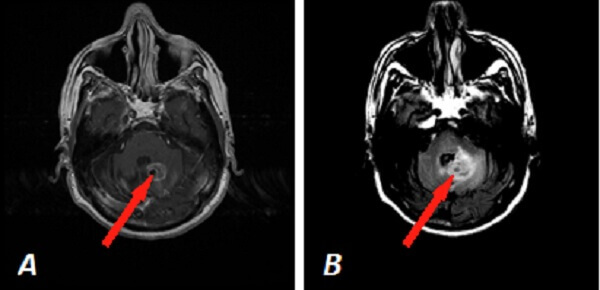

Diagnosis: Metastatic lung cancer to the cerebellum

Figure 1: Red arrow (a) and (b) Axial T1 post contrast and FLAIR images demonstrate a circumscribed intra axial enhancing mass in the left cerebellar hemisphere with surrounding vasogenic edema abutting the fourth ventricle. (C) 3D rotational MIP from a PET-CT scan demonstrates hypermetabolic right upper lobe pulmonary nodules consistent with lung cancer (in this case non small cell).